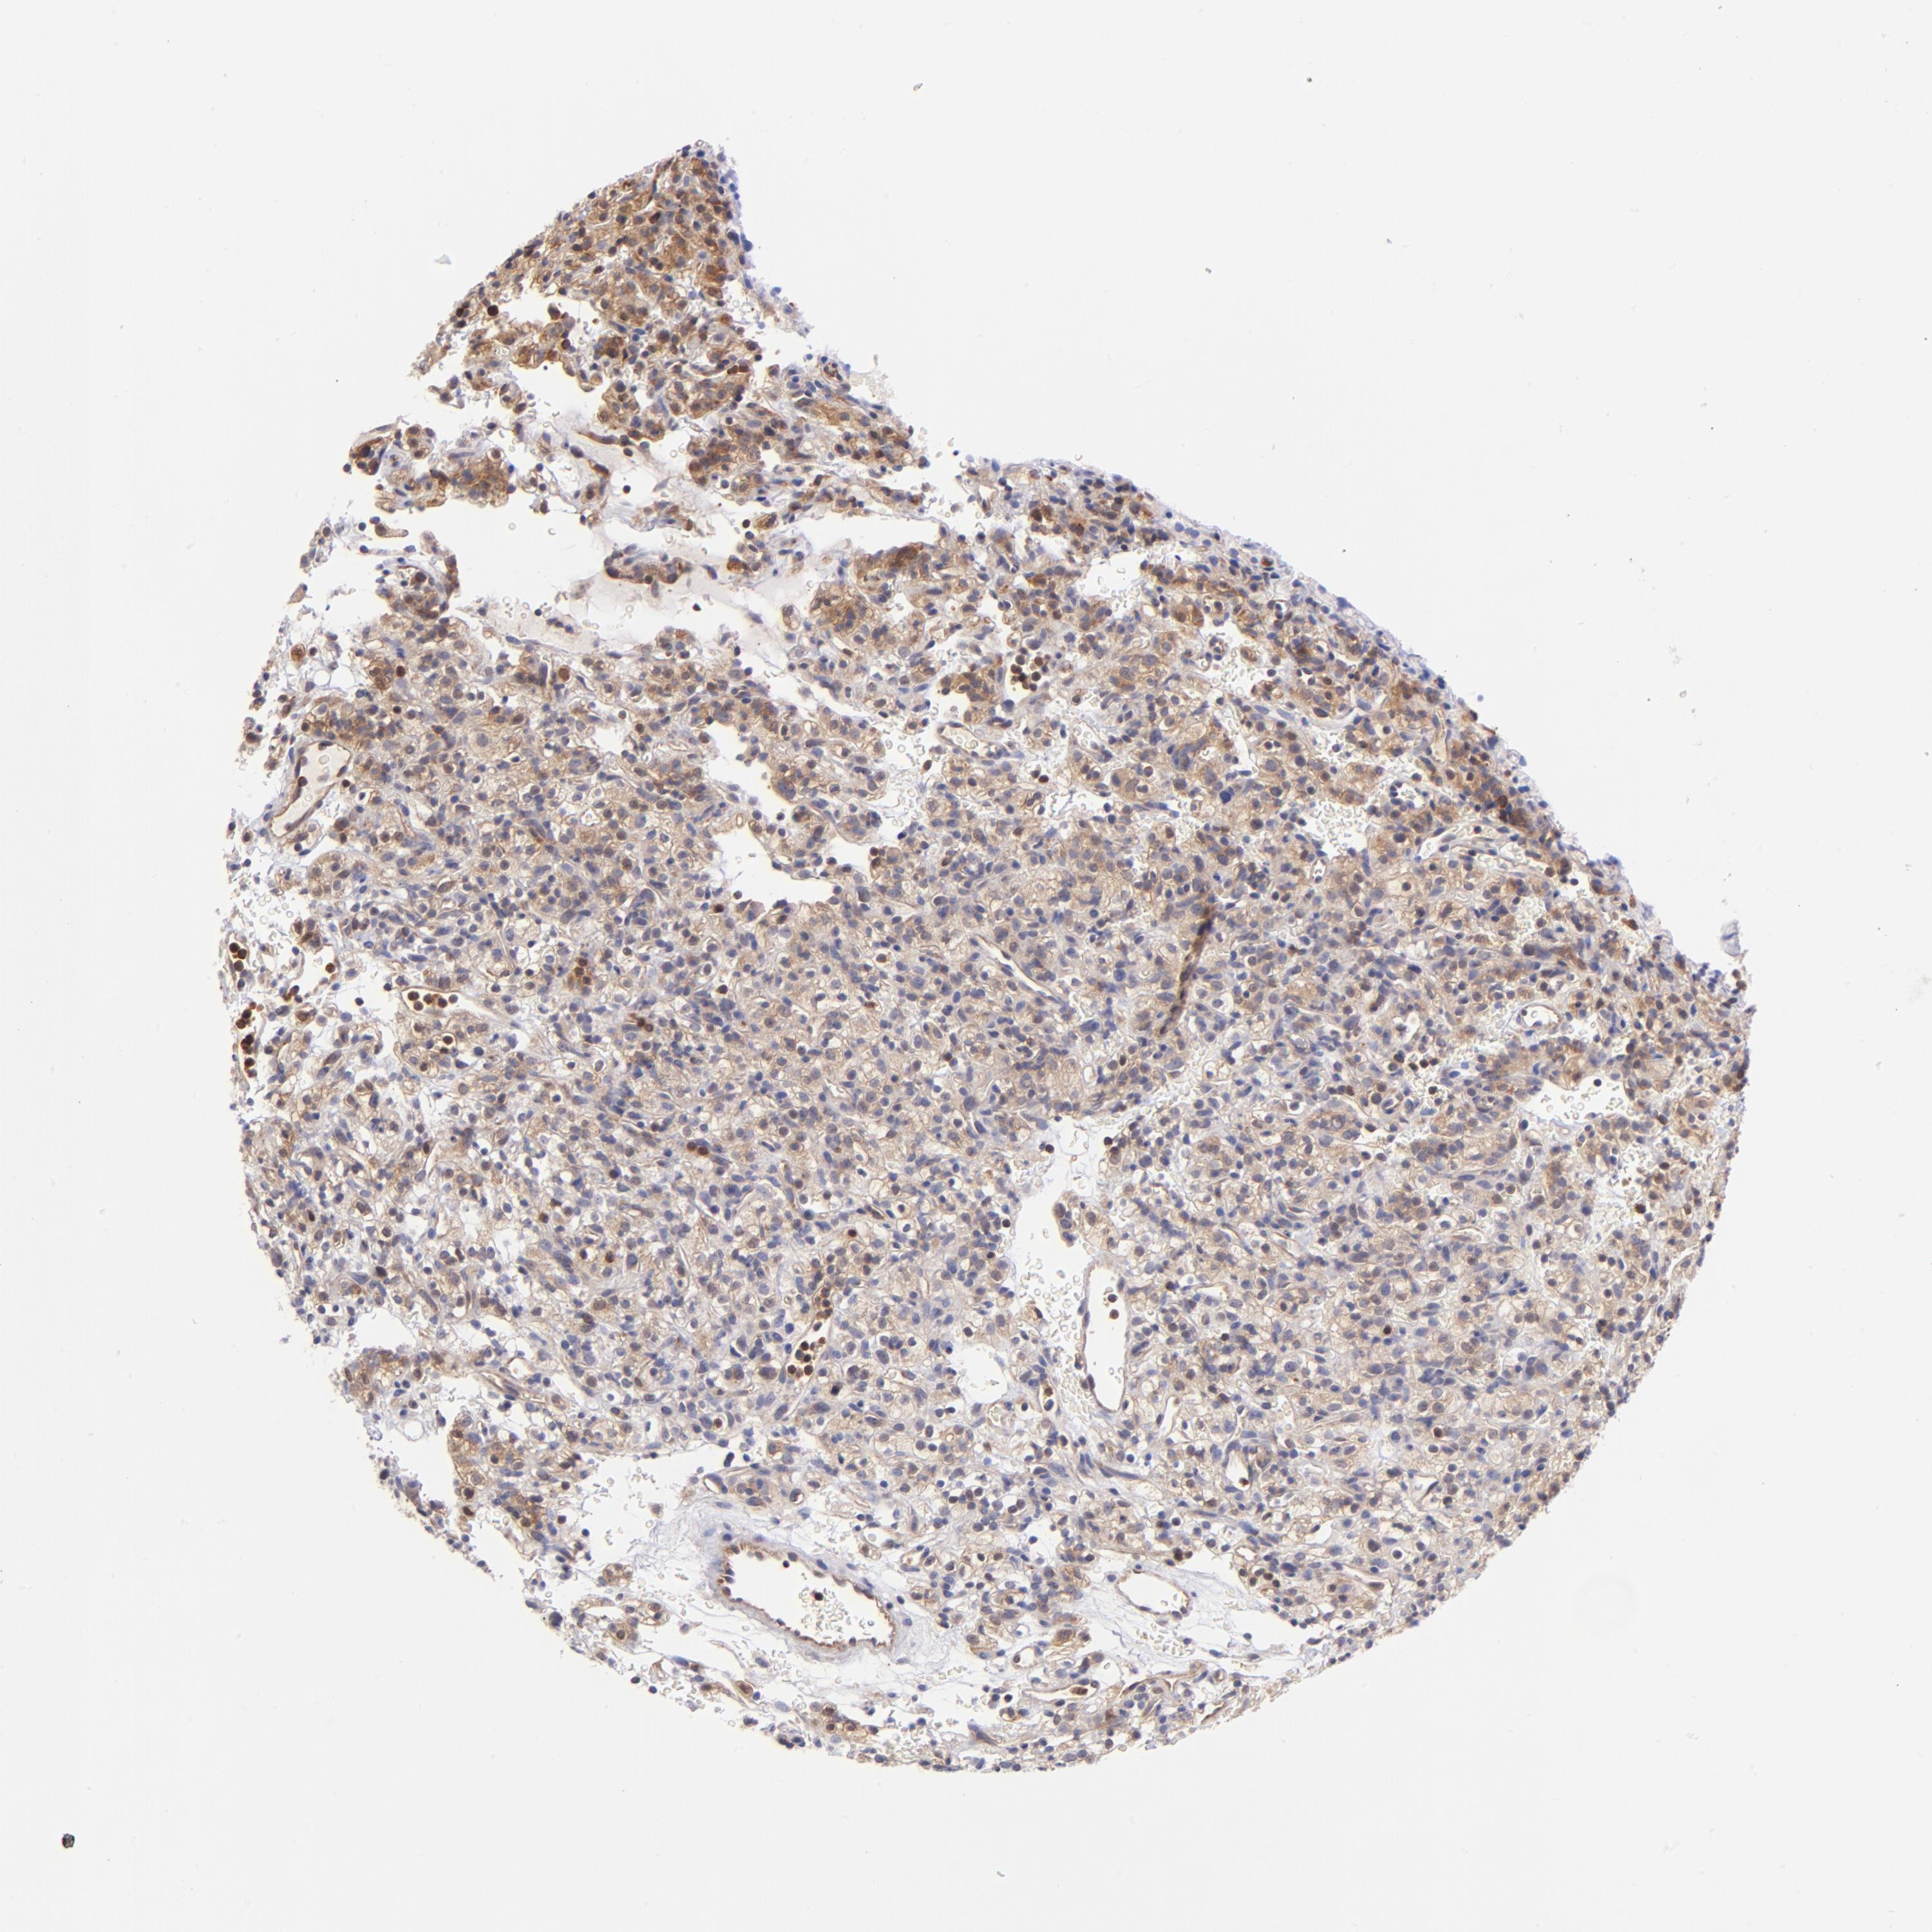

KIDNEY RENAL CLEAR CELL CARCINOMA (VALIDATION) - Interactive survival scatter ploti

The Survival Scatter plot shows the clinical status (i.e. dead or alive) for all individuals in the patient cohort, based on the same data that underlies the corresponding Kaplan-Meier plots. Patients that are alive at last time for follow-up are shown in blue and patients who have died during the study are shown in red.

The x-axis shows the expression levels (FPKM) of the investigated gene in the tumor tissue at the time of diagnosis. The y-axis shows the follow-up time after diagnosis (years). Both axes are complimented with kernel density curves demonstrating the data density over the axes. The top density plot shows the expression levels (FPKM) distribution among dead (red) and alive patients (blue). The right density plot shows the data density of the survived years of dead patients with high and low expression levels respectively, stratified using the cutoff indicated by the vertical dashed line through the Survival Scatter plot. This cutoff is automatically defined based on the FPKM cutoff that minimizes the p-score. The cutoff can be changed by dragging the vertical line or by entering a cutoff value in the square labeled "Current cut-off".

Under the Survival Scatter plot the p-score landscape (black curve; left axis) is shown together with dead median separation (red curve; right axis). Dead median separation is the difference in median mRNA expression between patients who have died with high and low expression, respectively. It is calculated as follows: median FPKM expression of dead patients with high expression - median FPKM expression of dead patients with low expression. This is intended to aid the user in visually exploring custom cutoffs and the associated p-scores and dead median separation.

Individual patient data is displayed and can be filtered by clicking on one or more of the category buttons on the top of the page. Categories describing expression level and patient information include: high, low, alive, dead, female, male and tumor stages. The scale of the x-axis can be toggled between linear and log-scale by clicking on the "x log" button. Mouse-over function shows TCGA ID, patient information and mRNA expression (FPKM) for each patient.

& Survival analysisi

Kaplan-Meier plots summarize results from analysis of correlation between mRNA expression level and patient survival. Patients were divided based on level of expression into one of the two groups "low" (under cut off) or "high" (over cut off). X-axis shows time for survival (years) and y-axis shows the probability of survival, where 1.0 corresponds to 100 percent.

YWHAB is not prognostic in Kidney Renal Clear Cell Carcinoma (validation)

Best expression cut offi

Based on the FPKM value of each gene, patients were classified into two groups and association between prognosis (survival) and gene expression (FPKM) was examined. The best expression cut-off refers the FPKM value that yields maximal difference with regard to survival between the two groups at the lowest log-rank P-value. Best expression cut-off was selected based on survival analysis .

When clicking on this number, the vertical dashed line indicating cut-off, the interactive survival plot, and the Kaplan-Meier curve will be adjusted to show results based on the best expression cut-off.

: 191.09

P scorei

Log-rank P value for Kaplan-Meier plot showing results from analysis of correlation between mRNA expression level and patient survival.

N/A

TCGA RNA samplesi

RNA-seq data is reported as average FPKM (number Fragments Per Kilobase of exon per Million reads), generated by the The Cancer Genome Atlas (TCGA) .

Normal distribution across the dataset is visualized with box plots, shown as median and 25th and 75th percentiles. Points are displayed as outliers if they are above or below 1.5 times the interquartile range. FPKM values of the individual samples are presented next to the box plot.

Average pTPM 160.7

Number of samples 100